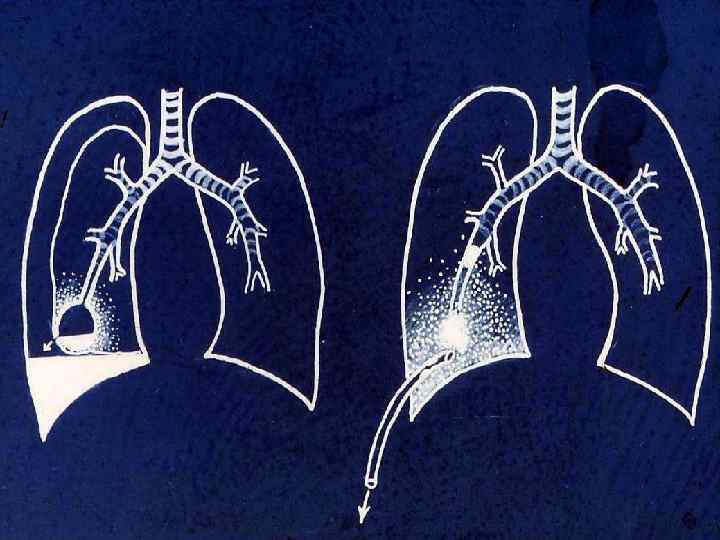

Бактериальная деструкция легких у детей презентация - 88 фото